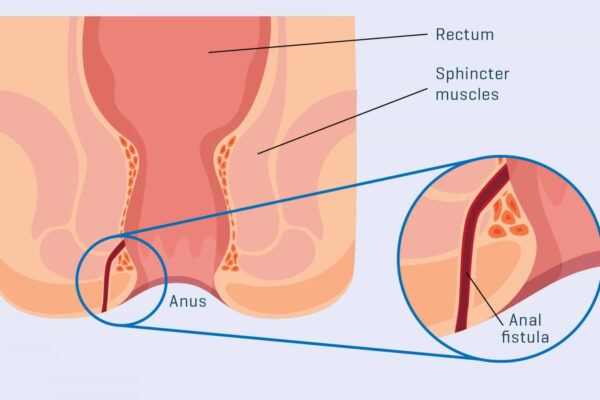

Overview

Package includes:

Days in hospital : 2 to 3 Days (For patient and one attendant)

Days in hotel : 7 Days (For patient and one attendant)

Room type in hospital : Shared

Room type in hotel : Private

Hotel category: Standard

Value added benefits of the Anal Fitsula:

Ø Doctor consultation charges

Ø Lab tests and diagnostic charges

Ø Room charges inside hospital during the procedure

Ø Surgeon Fee

Ø Nursing charges

Ø Hospital surgery suite charges

Ø Anesthesia charges

Ø Routine medicines and routine consumables (bandages, dressings etc.)

Ø Food and Beverages inside hospital stay for patient and one attendant.

Extra benefits:

ü Interpreter

ü Visa assistance

Ø Site tourism of the city

Ø Follow up with the doctor

Ø Airport pick up and drop

Ø Free online consultation with the doctor

Ø Priority appointments with the doctor

Ø Room upgrade from sharing to private